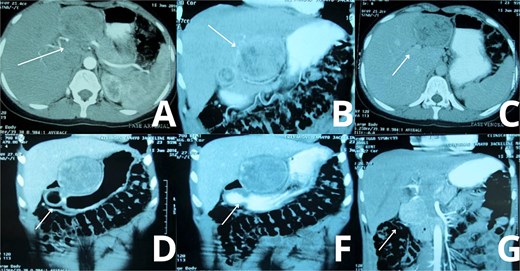

A contrast-enhanced triphasic abdominal computed tomography (CT) scan demonstrated a 10 cm isodense mass in hepatic segment 3, adjacent to the lesser curvature of the stomach (Fig. 1) The mass exhibited peripheral enhancement but lacked internal contrast uptake. There was no ascites, hepatosplenomegaly, or evidence of other hepatic lesions. The gallbladder was absent, consistent with previous cholecystectomy, and a small fluid collection was seen at the gallbladder bed.

Abdominal CT imaging suggestive of gossypiboma. Contrast-enhanced abdominal CT scans of the patient demonstrate a well-defined, heterogeneous mass located in the upper abdomen, specifically in hepatic segment 3. (A, C) Axial views reveal internal air foci and a linear radiopaque marker, highly suggestive of a retained surgical sponge (gossypiboma). (B) A transverse section further supports the presence of a foreign body, with peripheral enhancement and absence of internal contrast uptake. (D, F, G) Wider axial slices show the spatial relationship of the mass with surrounding hepatic and gastric structures, confirming its intrahepatic location and size (~10 cm), without evidence of ascites or other hepatic lesion.